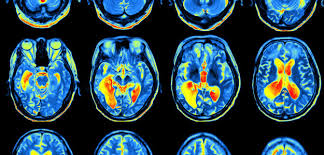

A groundbreaking study just published in PAIN Reports (2025) is confirming what I’ve been observing clinically for years. The researchers found something remarkable: people with chronic lower back pain don’t just have different spines—they have different brain activity patterns. Not because they’re imagining the pain, but because pain changes how the nervous system processes information.

The research team led by Keita Ueno studied 34 people with chronic low back pain and compared their brain activity to 34 people without pain. They used EEG technology to measure two crucial things:

They found that people with chronic back pain showed significantly reduced communication between key brain regions—specifically in the beta frequency range (21.5-30 Hz). Think of it like this: your brain has different “departments” that need to talk to each other to process pain appropriately. In chronic pain sufferers, those phone lines weren’t working as well.

Even more revealing: they found that certain slow-wave brain activity (theta and delta waves) correlated directly with pain intensity. The more of this slow-wave activity in the prefrontal cortex, the worse the pain.

But the real kicker? One specific connection—between the right prefrontal cortex and right auditory cortex—showed a 0.62 correlation with pain intensity. That’s huge in research terms. The more “wired” those regions were, the worse people felt.

The study identified specific brain areas with altered connectivity:

These aren’t random regions. These are the exact areas that determine how you experience and respond to pain.

When these regions aren’t communicating properly, your nervous system can’t accurately distinguish between actual threat and false alarm. The result? Pain that persists even when structural healing has occurred.